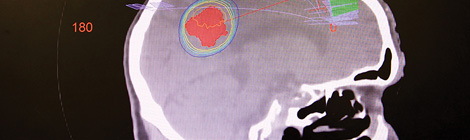

IT’S a persistent belief that the only treatment for brain cancer is to go under the knife, but Dr Chris Harper and his team have been effectively treating hard-to-reach metastatic brain tumours and other lesions with “stereotactic radiosurgery”. There are no incisions, and no heavy doses of radiation in stereotactic radiosurgery (SRS), which sends several…